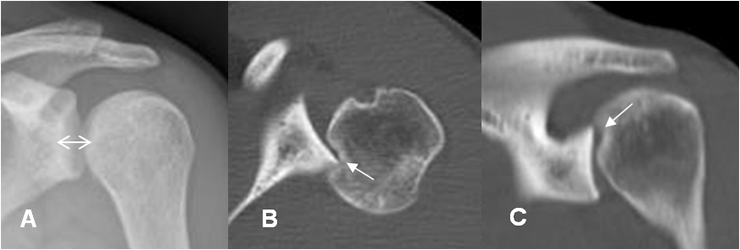

Fig 72 A. Bankart invertido.

A: Rx AP. Incremento del espacio glenohumeral, por luxación posterior.

B: TAC axial y C: TAC reconstrucción sagital. Luxación glenohumeral posterior, con fractura impactada de la cabeza humeral, en la glenoides posterior.